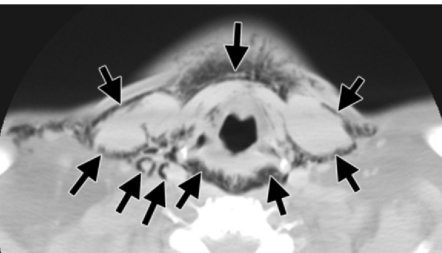

Abcès submandibulaire

- Premier site d’abcès odontogène

- Chercher l’ostéomyélite de l’os adjacent

Abces sous-periostié mandibulaire suite a extraction dentaire